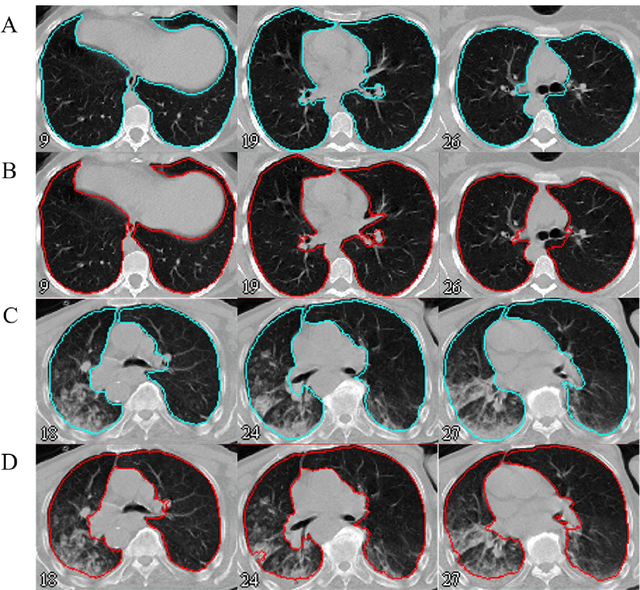

Abstract:Automated semantic image segmentation is an essential step in quantitative image analysis and disease diagnosis. This study investigates the performance of a deep learning-based model for lung segmentation from CT images for normal and COVID-19 patients. Chest CT images and corresponding lung masks of 1200 confirmed COVID-19 cases were used for training a residual neural network. The reference lung masks were generated through semi-automated/manual segmentation of the CT images. The performance of the model was evaluated on two distinct external test datasets including 120 normal and COVID-19 subjects, and the results of these groups were compared to each other. Different evaluation metrics such as dice coefficient (DSC), mean absolute error (MAE), relative mean HU difference, and relative volume difference were calculated to assess the accuracy of the predicted lung masks. The proposed deep learning method achieved DSC of 0.980 and 0.971 for normal and COVID-19 subjects, respectively, demonstrating significant overlap between predicted and reference lung masks. Moreover, MAEs of 0.037 HU and 0.061 HU, relative mean HU difference of -2.679% and -4.403%, and relative volume difference of 2.405% and 5.928% were obtained for normal and COVID-19 subjects, respectively. The comparable performance in lung segmentation of the normal and COVID-19 patients indicates the accuracy of the model for the identification of the lung tissue in the presence of the COVID-19 induced infections (though slightly better performance was observed for normal patients). The promising results achieved by the proposed deep learning-based model demonstrated its reliability in COVID-19 lung segmentation. This prerequisite step would lead to a more efficient and robust pneumonia lesion analysis.